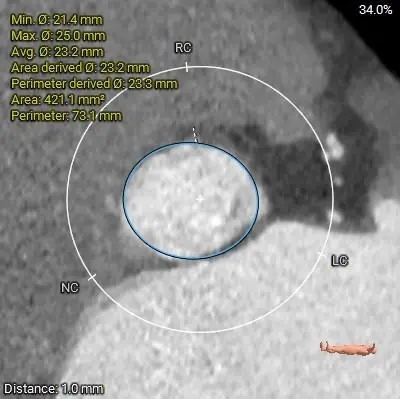

主动脉根部测量

周长径23.8

周长径27.1

L:32.9 N:33.3 R:27

周长径25.3

周长径31

瓣膜轻微增厚

无钙化

三叶瓣纯反流

瓣环23.8

瓣叶轻微增厚、无钙化

流出道27.1mm,敞口型

瓣上结构测量

周长径23.3

周长径23.4

周长径23.78

周长径23.9

周长径24

周长径24.4

瓣叶轻微增厚,瓣上多平面可参与锚定

冠脉风险评估

LCA Height 14.1mm

RCA Height 16.3mm

LCA & Leaflet 14.9mm&11.6mm

RCA & Leaflet 13.7mm&12.7mm

瓣环水平夹角49度,非横位心

冠脉高度可,瓣叶不长,冠脉阻挡风险不高